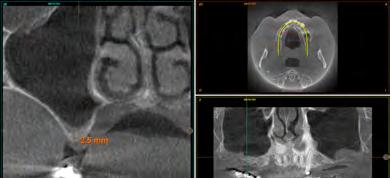

maxilares, lo que apunta a la existencia de una atrofia vertical ósea excesiva en esta área que pretende ser rehabilitada con implantes dentales (Figura 5). A mayor aumento vemos la fractura radicular de la pieza 13 que ha generado el defecto circunferencial (Figura 6) y en el cone beam de planificación se constata y además se pone de manifiesto la dimensión del defecto óseo y el volumen óseo residual a nivel palatino de 2 mm (Figura 7).

En el estudio pormenorizado del cone beam superior se constata la extrema atrofia ósea vertical en ambos sectores posteriores del maxilar que hace necesaria la elevación de seno bilateral, por abordaje convencional (Figura 8 y 9). En el seno izquierdo, el abordaje debe ser mayor al necesitar un injerto de mayor volumen (desde la zona de premolares hasta molares) por lo que la ventana de acceso de mayor longitud se conserva en Endoret-PRGF durante la cirugía para ser utilizada posteriormente como membrana ósea. En el seno del primer cuadrante, la elevación se lleva a cabo para el área molar en exclusiva. La ventana de acceso al seno maxilar izquierdo se coloca en vestibular del defecto generado tras la exodoncia de la pieza dental 13,

Figura 5. Radiografía inicial del paciente. En ella observamos el defecto crateriforme del diente 13 y una neumatización excesiva de ambos senos maxilares en el maxilar posterior donde se pretenden realizar implantes dentales. Figura 6. Imagen en detalle de la pieza 13. En esta imagen cercana podemos observar una fractura vertical evidente en el área del ápice ya en este tipo de prueba radiológica. Figura 7. En el cone-beam de planificación se objetiva la fractura y el defecto crateriforme con pérdida de la tabla vestibular completa y un remanente óseo a nivel palatino de 2 mm para la posterior inserción de un nuevo implante.